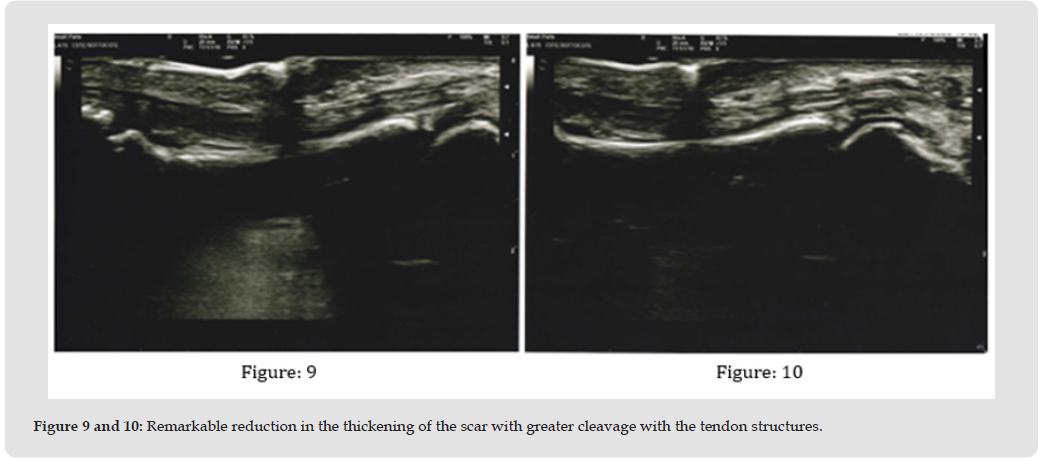

All patients responded positively to the therapy, showing an increased extension of the treated fingers and a softer and more elastic tissue from the very first treatment application. The echographies showed a reduction in the thickening of the scar and its fibrosis combined with an increased cleaving of the tendon structures. The infrared camera detected a significant difference between the maximum temperature of the fingers (36.4 °C) and the retracted finger, which average temperature was 34.8 °C before therapy. After the treatment cycle, the maximum temperature of the hand was stable (36.5 °C) while that of the suffering finger increased to 35.6 °C, demonstrating a more uniform vascularization of tissues. DASH assessment score provided crucial information on functional recovery of the fingers/hands, as before the treatment the average level was 37.33 (from 32.50 to 42.75) while after the cycle of sessions it reduced to an average value of 11.66 (from 6.50 to 16.75), with a significant average improvement of 25.67 (equal to 68.77%).The average comfort level was 7.71 (from 7 to 9), showing that the patients considered the treatment pleasant and relaxing. VAS scale before the treatment cycle showed an average level of pain of 3.01 (from 2.1 to 3.5), after therapy it lowered to an average value of 1.07 (from 0 to 1.8) showing a significant average improvement (-1.94 equal to -64.5%). The follow-ups performed six months later showed a slight improvement of the VAS scale (average value 0.88, minimum 0, maximum 1.5) and stabilization of the DASH score. No subject experienced side effects, not even minor ones, during the treatments and all of them could immediately resume their normal lifestyles without any restrictions.

This study was developed by combining retrospective experiences of the various authors who casually found to have had similar outcomes on patients treated for scars on the palm of the hands, also burdened by Dupuytren’s contracture, and who then retrieve all the documentation provided in this study. The fortuitousness of this discovery hindered the preparation of a study plan with certain parameters for patient enrollment, such as patient splitting into homogeneous groups in order to compare results with greater precision; however, the authors have decided to stick to those parameters in order to recruit a significant number of patients to see if the results obtained will be confirmed on a large scale. The analysis of the collected data is positive and potentially preferable to existing state-of-the-art therapies, at least for the first six months. If on the one hand more sessions are required (in our case we have provided between 3 and 7), on the other the immediate recovery of full activity by the patients, absence of pain, downtime or restrictions to regular lifestyles as well as greater relaxation of the fingers were appreciated already from the first session. A clear improvement of the pathology with total stabilization over six months was proven by all the assessment scales adopted; this makes us optimistic in view of a larger clinical study. The total absence of side effects, already demonstrated by VEMFtherapy in scars treatment [39,43-46] was also appreciated. Analysis of the existing literature suggests that the combined action between electromagnetic fields and negative pressure has an important effect on the remission of fibrosis [39,43] as has also been shown by the separate use of electromagnetic fields, although in different fields [36-38] and negative pressure, which mechanical action promotes a series of reactions in terms of mechanotransduction [21,22,44,45] by converting mechanical stimuli into biochemical signals that activate a series of cascade reactions, reducing the compactness and strength of the fibrous component. In our opinion, the anti-inflammatory action of the electromagnetic fields is particularly relevant, as these lead to an increase in the production of IL-10 anti-inflammatory cytokines 46, analogously to what has been documented with negative pressure [28] (Figures 6-10).